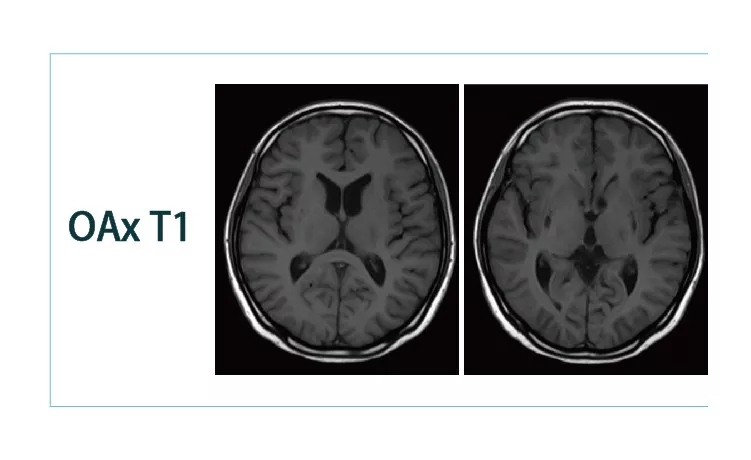

1544579634898245.jpg1544579646797662.jpg